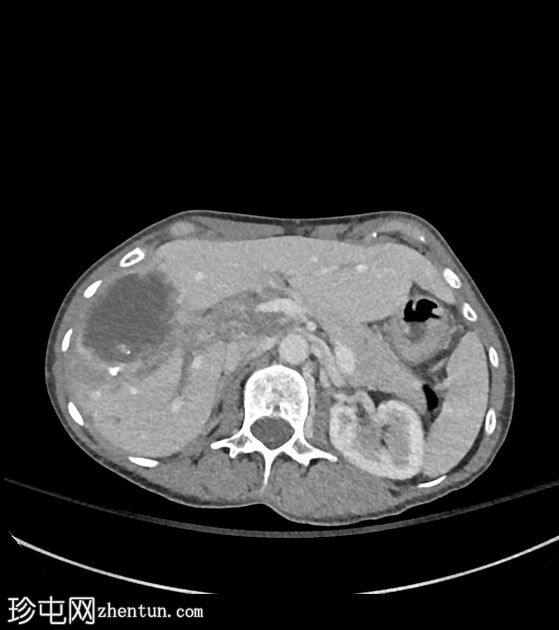

CT扫描

2.jpeg

轴向C+期

动脉期

3.jpeg

门静脉期

肝段VIII区中心可见一囊性坏死灶,边缘不规则,周围可见粗钙化,造影后无明显强化。轻度包膜回缩及邻近灌注改变。肝穹窿内可见其他较小的卫星囊性灶和多处粗钙化。肝门部可见浸润性组织,部分钙化,导致门静脉轻度狭窄和右侧肝内胆管轻度扩张。

CT表现符合肝泡包虫病。